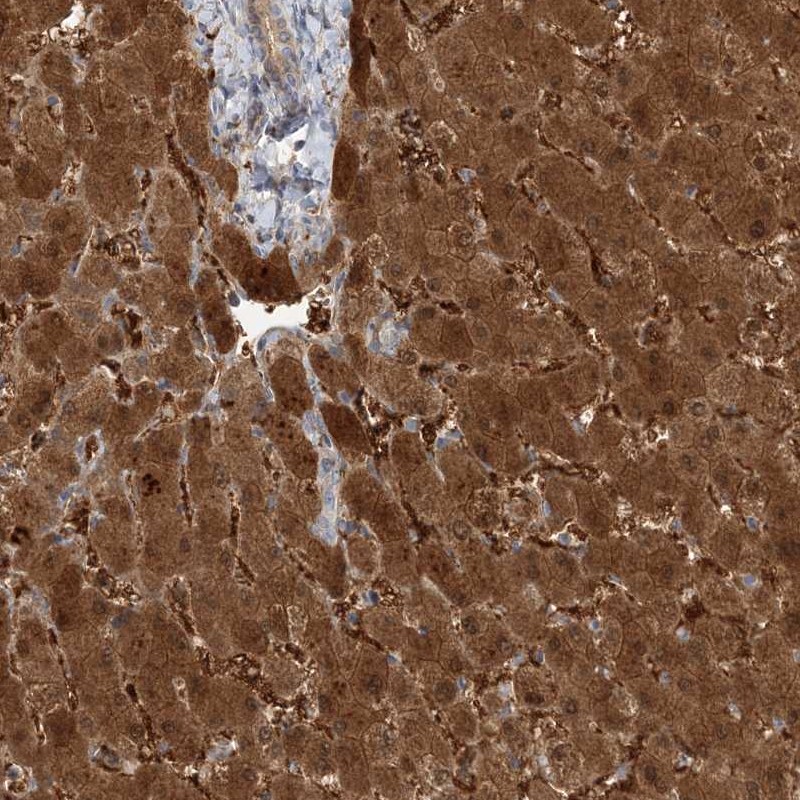

Immunohistochemistry analysis in human liver and pancreas tissues using Anti-HAAO antibody. Corresponding HAAO RNA-seq data are presented for the same tissues.